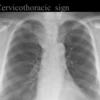

Cervicothoracic sign

(Thyroid mass- see next image)